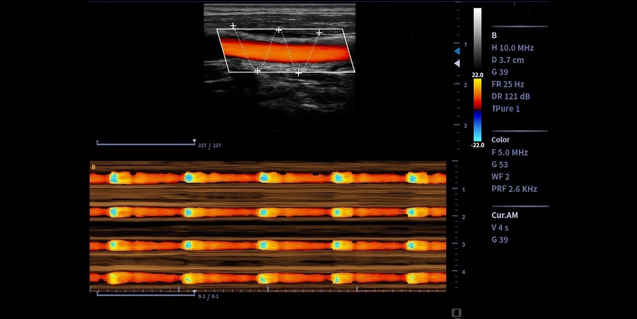

微血流技术 Micro Flow

- 微血流成像技术基于时间,空间和参数信息共同检测血流,可提高对低速血流的灵敏度,有效抑制非血流信号的干扰

-

新BF技术:16倍波束合成,数据处理速率提高16倍,每次发射可获得16帧图像

A.提高帧率从而提高运动组织的检测灵敏度

B.提高整场分辨率,穿透力和对比度

临床图像